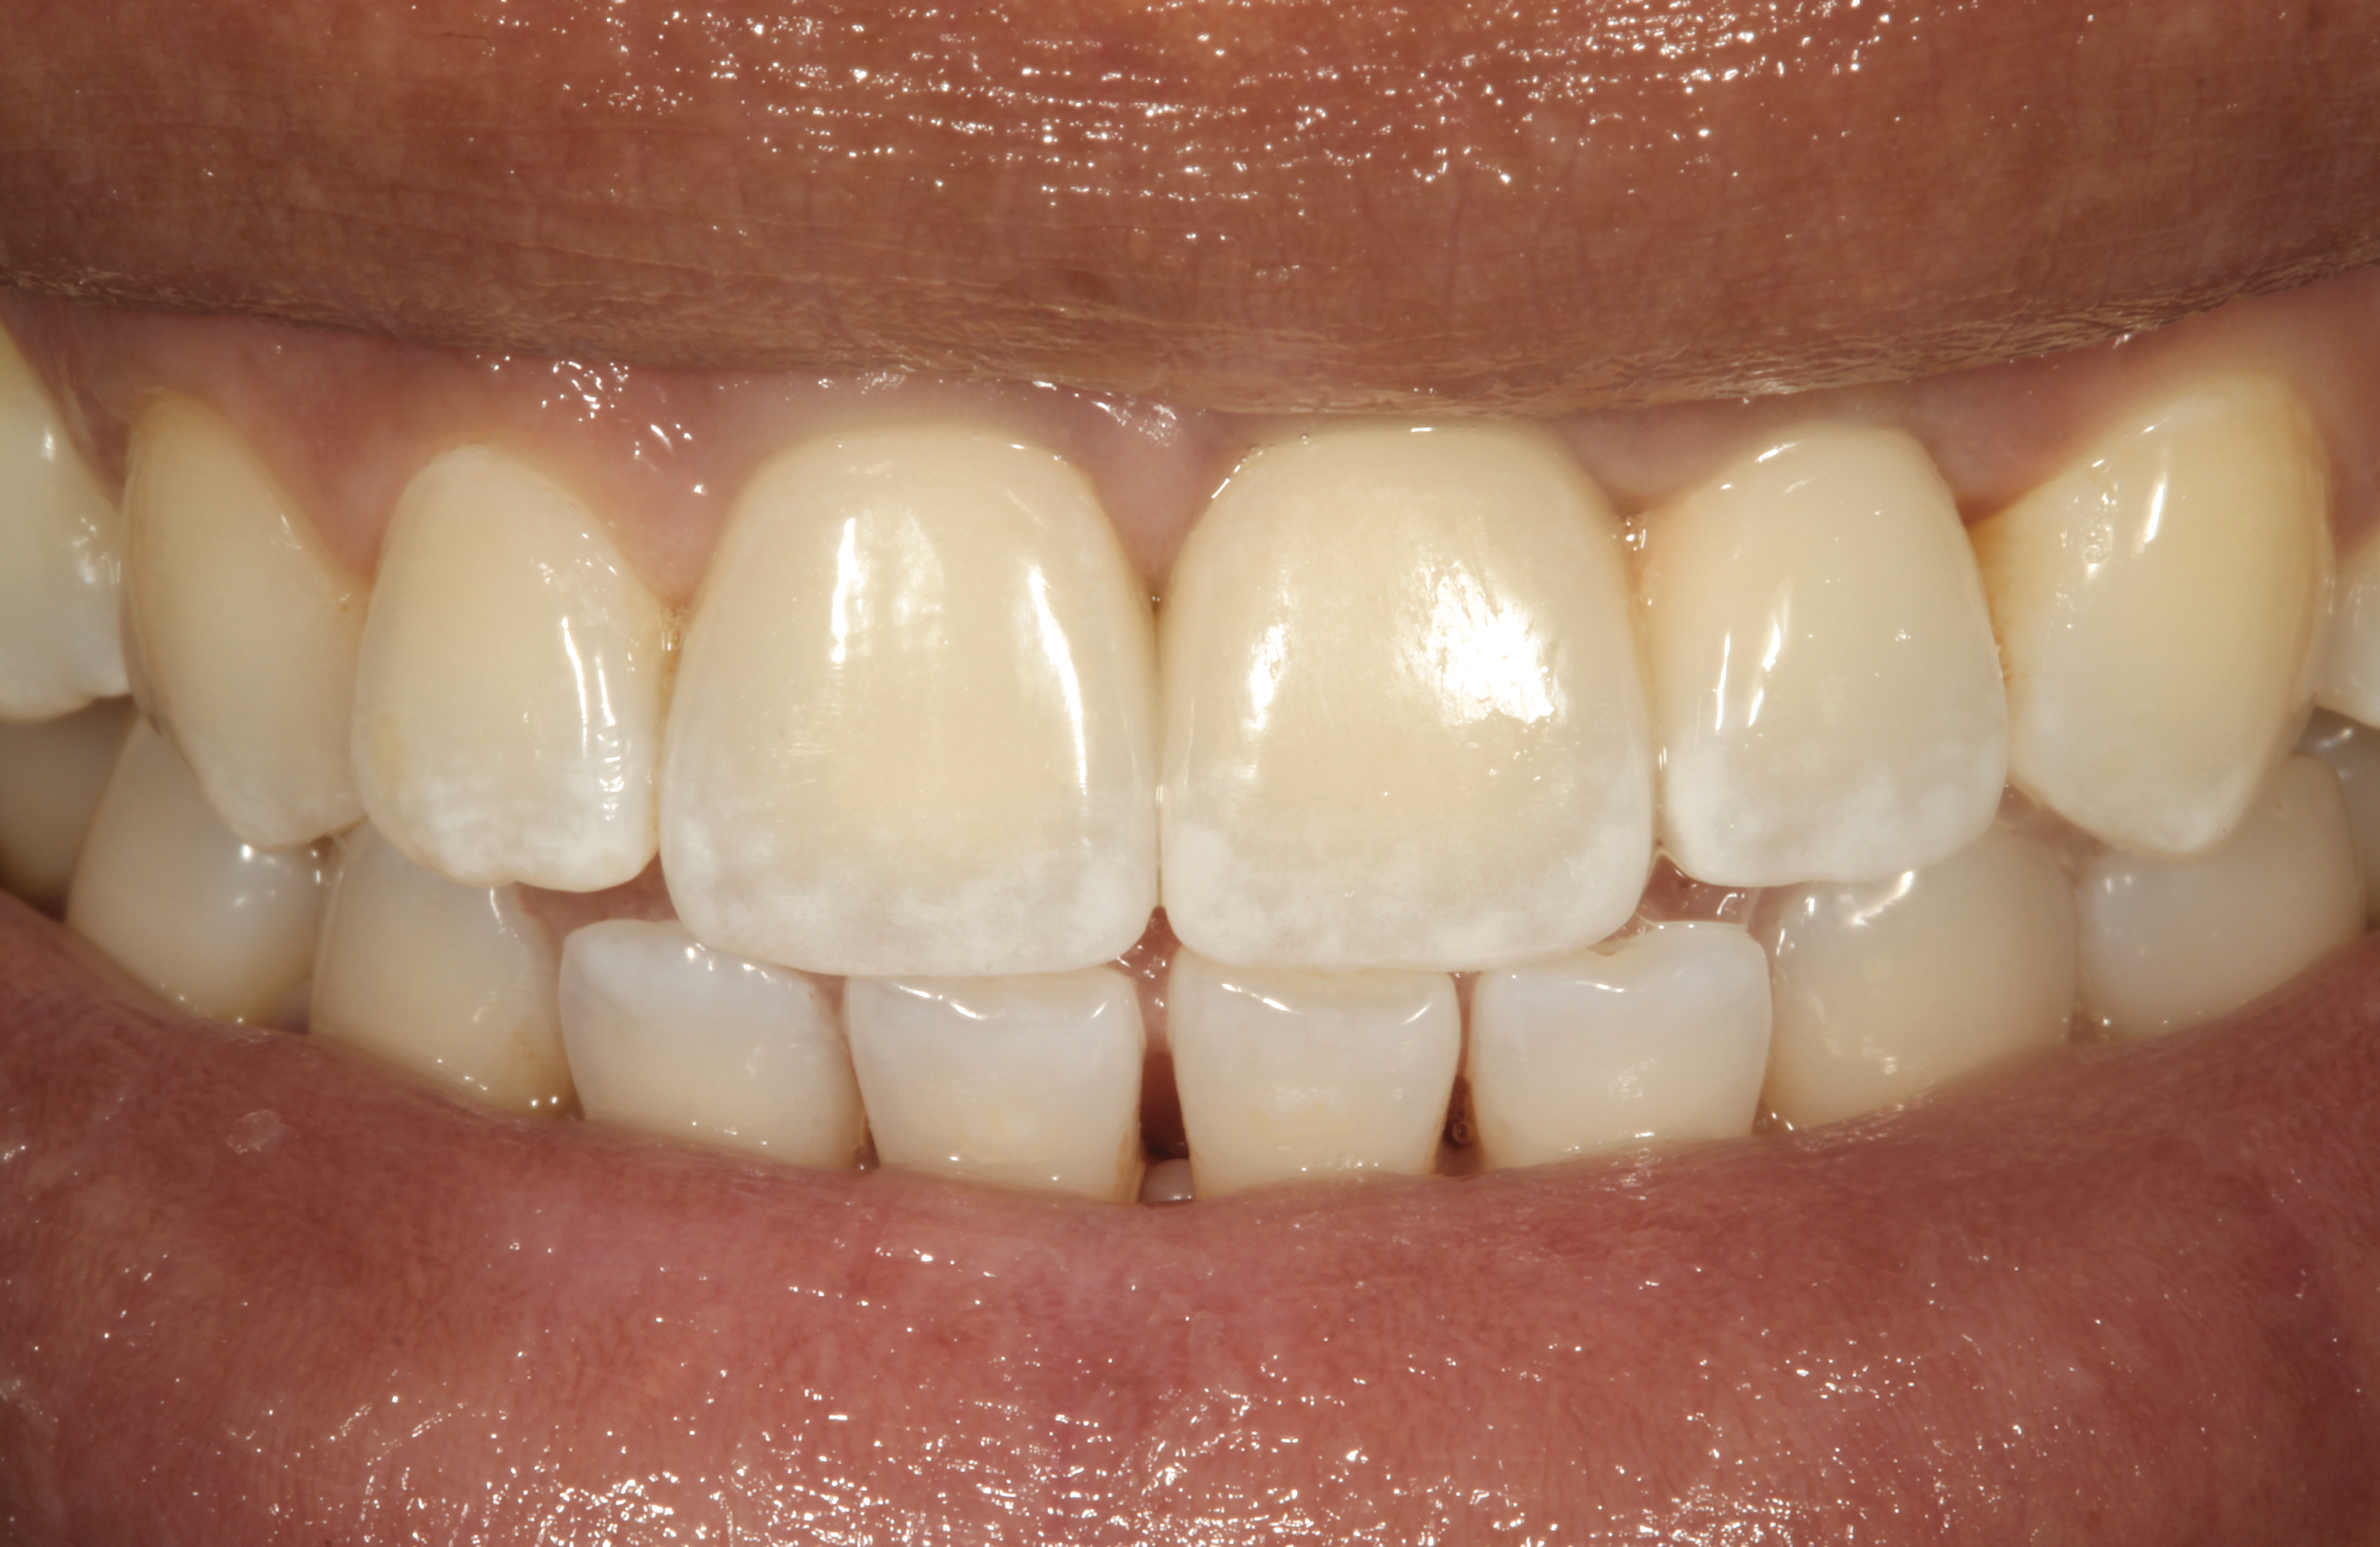

The crown and screw-retained custom abutment were removed, and a surgical cover screw was placed into the implant, thereby allowing spontaneous gingival augmentation in situ (Figure 33 and Figure 34). Note that the lingual aspect of the implant site was significantly more coronal than the labial aspect, which was positive because the defect would be limited to a facial–lingual defect. A fixed RBR bridge was cemented on the adjacent teeth and used as a tooth-supported transitional provisional restoration (Figure 35). A few weeks were allotted to let the soft tissue heal and migrate around the cover screw (Figure 36) to see if there would be complete coverage, thereby allowing a soft-tissue augmentation procedure to be performed with primary flap closure as in clinical scenario No. 2. The major obstacle in achieving a positive tissue response was that the implant depth was also deficient because the implant–abutment connection was at the level of the free gingival margin. It was decided that the best treatment option would be to remove the implant. A high-powered reverse-torque device (Fixture Remover Kit, NeoBiotech, www.neobiotechus.com) was used to remove the implant atraumatically (Figure 38 through Figure 41). The implant socket was allowed to heal for several months not unlike an extracted tooth (Figure 42). A new implant was placed in a better position from both a restorative and esthetic perspective (Figure 43), and after a few months of healing, a new crown was made (Figure 44). A satisfactory functional and esthetic result was achieved (Figure 45 and Figure 46) without employing pink porcelain.

Fig 45. The definitive crown tooth No. 26 seated in place and provisionally cemented. The recession defect was eliminated with the removal and replacement of a new implant in the proper position.

Figure 45